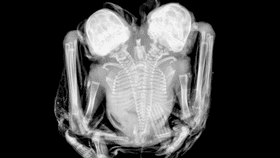

The researchers took X-ray images (below) of the bats to reveal they share two complete forelimbs and two complete hind limbs, just like a regular bat. However, they have two separate spines that branch down into a single lumbar region (the bottom of the spine).

For the record, they only have a single penis. However, ultrasonic images revealed they do have two separate similarly-sized hearts.